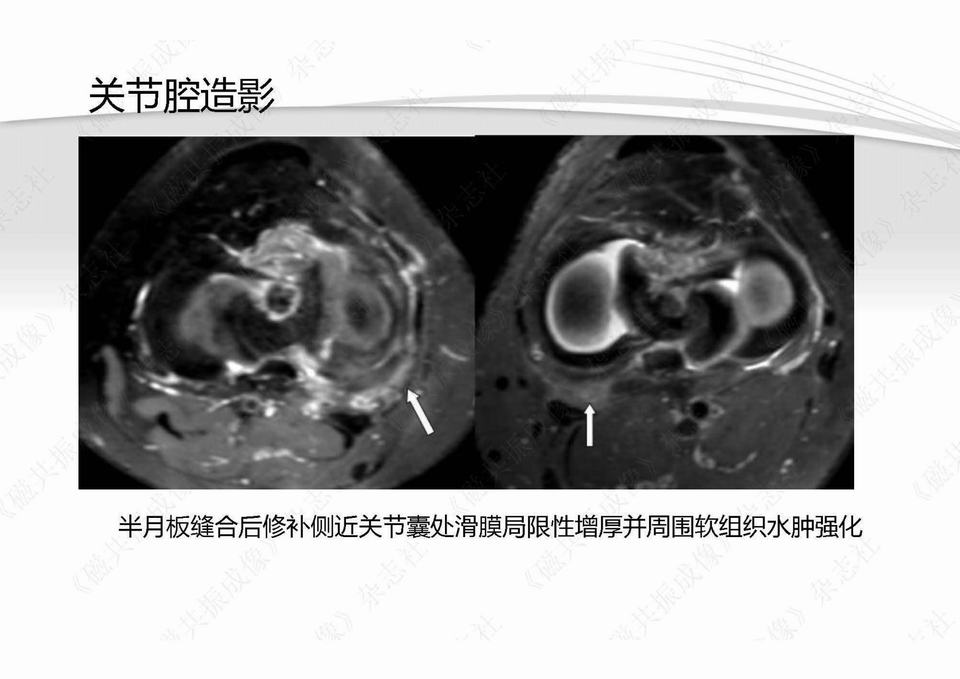

半月板损伤术前及修补术后MR影像学评价